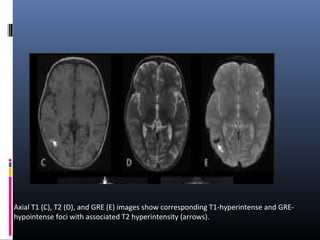

Axial T1 (C), T2 (D), and GRE (E) images show corresponding T1-hyperintense and GRE-

hypointense foci with associated T2 hyperintensity (arrows).